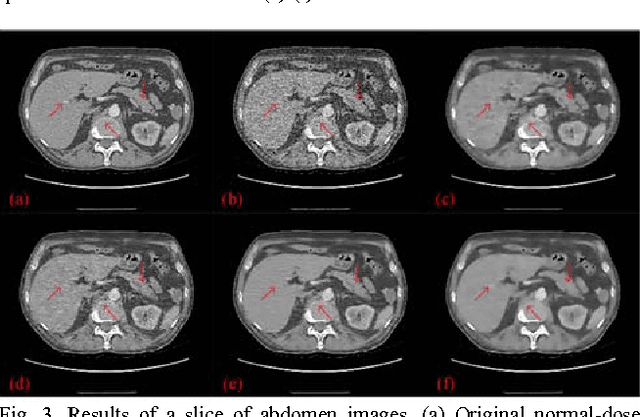

To reduce the potential radiation risk, low-dose CT has attracted much attention. However, simply lowering the radiation dose will lead to significant deterioration of the image quality. In this paper, we propose a noise reduction method for low-dose CT via deep neural network without accessing original projection data. A deep convolutional neural network is trained to transform low-dose CT images towards normal-dose CT images, patch by patch. Visual and quantitative evaluation demonstrates a competing performance of the proposed method.